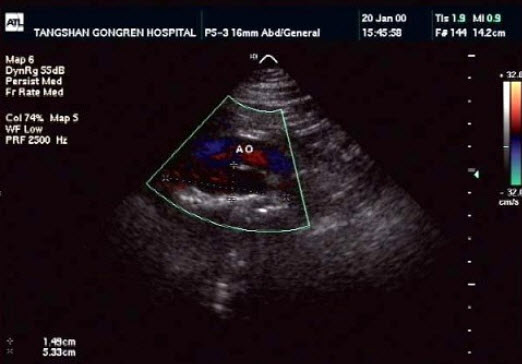

5、单项选择题

该病例最可能诊断()

A.真性动脉瘤

B.假性动脉瘤

C.夹层动脉瘤

D.以上都不是

E.主动脉瓣狭窄